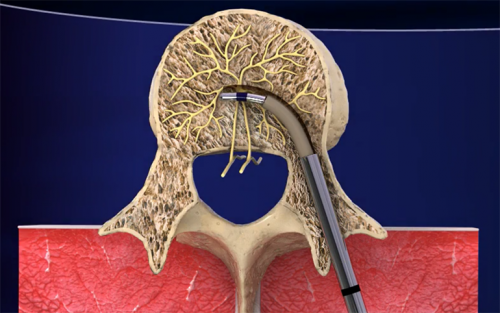

فالجراح أثناء هذه العملية يستخدم جهازًا صغيرًا لقتل العصب المسؤول عن آلام أسفل الظهر.

يستلقي المريض أولًا على وجهه لتلقي التخدير الموضعي في المنطقة الواقعة بين الفقرتين L3 و S1.

بعد ذلك، يتم إدخال إبرة دقيقة جدًا في هذه المنطقة لإيقاف نشاط العصب القاعدي. وذلك لأن العصب القاعدي يرسل إشارات الألم من العمود الفقري إلى الدماغ.

بذلك الإجراء السريع ومن خلال الجراحة الموضعية، يمكن تخفيف آلام أسفل الظهر.

يستخدم هذا العلاج طاقة ترددات راديوية. وهو ما يعني عدم استخدام الجراح للمشرط أثناء الجراحة التي لا تتسبب بأيّة جروح.

يرسل الجهاز طاقة الترددات الراديوية هذه ويشعر المريض بقليل من الحرارة فقط أثناء العملية.